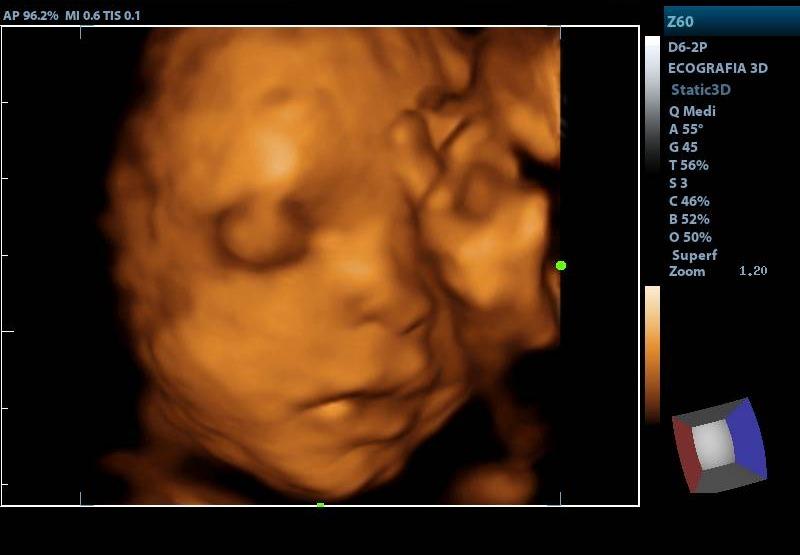

ECOGRAFIA OBSTETRICA 3D

SERVICIOECOGRAFIA

PRESENTACIÓNECOGRAFIA

CONDICIÓNCUALQUIER EDAD GESTACIONAL

TIEMPO20 MINUTOS

TIPO RESULTADOSIMAGENES ECOGRAFICAS

ESPECIFICACIONESIMAGEN TRIMIDENCIONAL DEL FETO SE ESTUDIA BIOMETRIA FETAL ILA VALORACION PLACENTA LATIDOS CARDIACOS FETALES